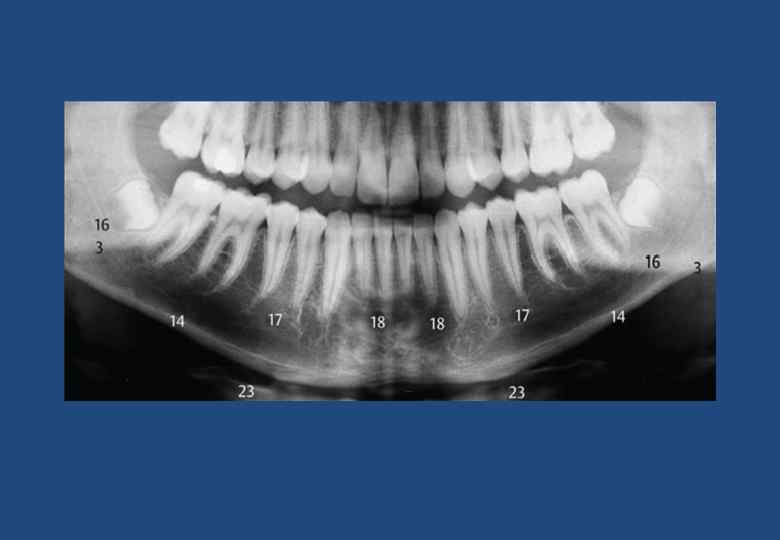

• • • • • • 1. Наружная косая линия (продолжение переднего края в каудальном и боковом направлениях) 2. Височный гребень с ретромолярным треугольником 3. Нижнечелюстное отверстие 4. Нижнечелюстной канал 5. Подбородочное отверстие 6. Угловой отросток на жевательной бугристости 7. Угол нижней челюсти 8. Компактное вещество в основании нижней челюсти 9. Подъязычная кость с ее большим рогом 10. Шейный отдел позвоночника с отчетливо видимыми замыкающими пластинами тел позвонков 11. Верхнечелюстная пазуха (границы) 12. Спинка языка 13. Медиальный полюс суставной головки 14. Латеральный полюс суставной головки 15. Венечный отросток в суперпозиции к крыловидному отростку, бугру верхней челюсти и тканям небной занавески 16. Шейка мыщелкового отростка 17. Небная занавеска 18. Тень крыши неба и тел носовых раковин 19. Верхний отдел глотки 20. Длинный оссифицированный шиловидный отросток 21. Тень компактного вещества противоположной стороны челюсти